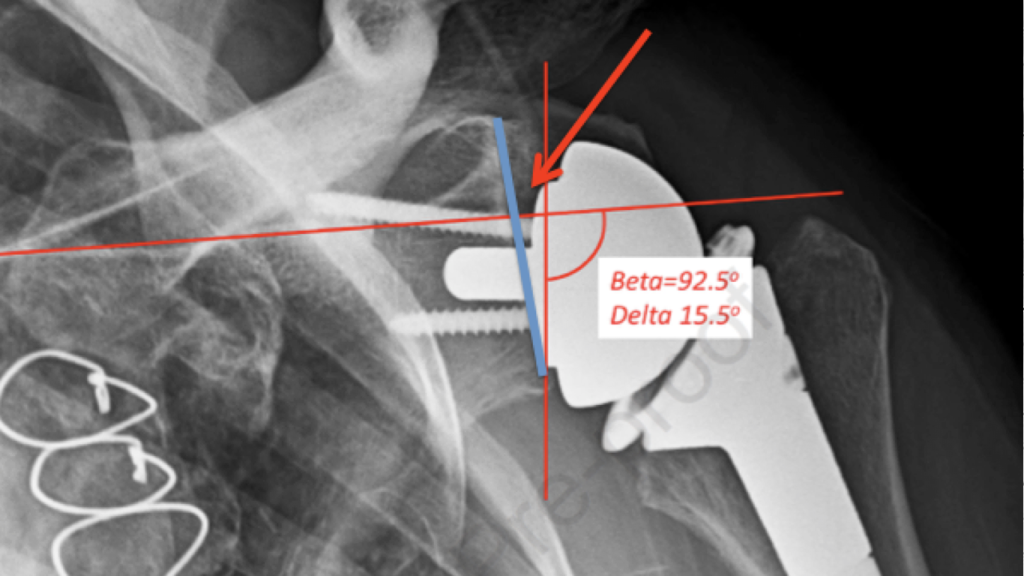

تشخیص دررفتگی کتف معمولاً با بررسی علائم بالینی و انجام تصویربرداری پزشکی صورت میگیرد. پزشک ابتدا با مشاهده تغییر شکل ظاهری شانه، بررسی دامنه حرکتی، و ارزیابی درد و تورم، به احتمال دررفتگی پی میبرد. سپس برای تأیید تشخیص، از تصویربرداریهایی مانند رادیوگرافی (X-ray) استفاده میشود تا محل دقیق استخوان و نوع دررفتگی مشخص شود. در موارد پیچیدهتر یا برای بررسی آسیب به بافتهای نرم، ممکن است MRI یا سیتیاسکن نیز تجویز شود. تشخیص دقیق و سریع، نقش مهمی در جلوگیری از آسیبهای ثانویه و انتخاب روش درمان مناسب دارد.